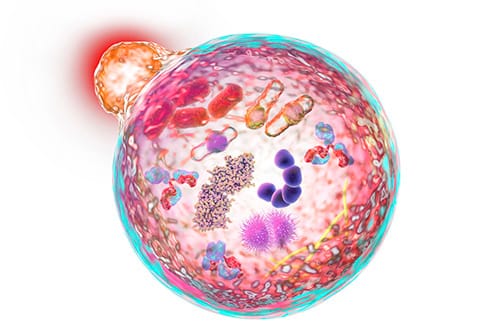

Nguyên nhân gây bệnh NPD được xác định là do thiếu hoặc không đủ enzym để phân hủy lipid trong tế bào, dẫn đến tích tụ lipid trong các mô và cơ quan trong cơ thể, gây ra các triệu chứng và biến chứng của bệnh. NPD được phân 3 loại (tuýp) A,B và C, loại C được coi là Alzheimer ở trẻ em.

Tuýp A và B là do một enzym bị thiếu hoặc bị trục trặc gọi là sphingomyelinase. Điều này ảnh hưởng đến khả năng chuyển hóa chất béo của cơ thể (cholesterol và lipid), dẫn đến tích tụ chất béo trong tế bào, gây ra rối loạn chức năng tế bào và theo thời gian, tế bào chết. Tuýp A xảy ra chủ yếu ở trẻ sơ sinh có biểu hiện bệnh não tiến triển nặng. Do không có cách chữa trị, vì vậy hầu hết trẻ em không sống quá vài năm, hầu hết tử vong từ 3 đến 5 tuổi. Tuýp B thường xuất hiện muộn hơn trong thời thơ ấu và không liên quan đến bệnh não nguyên phát. Hầu hết những người bị tuýp B có thể sống sót đến tuổi trưởng thành.

Đối với NPD tuýp C (NPD-C) hiếm gặp. Các đột biến di truyền của tuýp này khiến cholesterol và các chất béo khác tích tụ trong các cơ quan như gan, lách hoặc phổi. Não bộ cuối cùng cũng bị ảnh hưởng. Khi đó trẻ có các biểu hiện về trí nhớ, vận động, phối hợp cơ bắp,… khiến hoạt động của người bệnh luôn "khó nhọc, vụng về". Về lâu dài, NPD-C gây ra suy giảm kỹ năng vận động độc lập như: đi đứng, chạy nhảy, thoái hóa, suy giảm nhận thức… khiến người bệnh không thể điều khiển được bản thân theo ý muốn, không thể làm việc mà mình muốn.